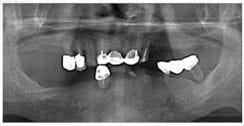

X 光片

術前X光片

術後X光片